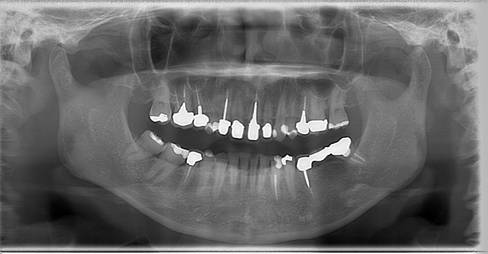

歯周病で抜歯せざるを得ず、インプラントを希望されたケース(使用インプラントはスプライン)

術前。すべての歯が歯周病の末期状態でブリッジ全体がうごいて噛めないとの訴え。右上の犬歯が腫れていました

固定式のブリッジが入っていましたが歯周病で動いています

下顎前歯部には歯石の沈着がみられます

術前パノラマレントゲン写真。根の周りが黒くなり、骨がなくなっていることがわかります